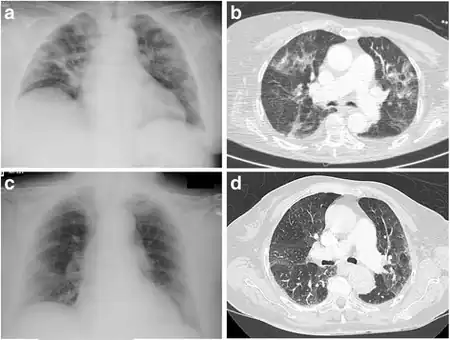

Eosinophilic pneumonia is diagnosed in one of three circumstances: when a complete blood count reveals increased eosinophils and a chest X-ray or computed tomography identifies abnormalities in the lungs, when a biopsy identifies increased eosinophils in lung tissue, or when increased eosinophils are found in fluid obtained by a bronchoscopy (bronchoalveolar lavage fluid). Association with medication or cancer is usually apparent after review of a person's medical history. Specific parasitic infections are diagnosed after examining a person's exposure to common parasites and performing laboratory tests to look for likely causes. If no underlying cause is found, a diagnosis of acute or chronic eosinophilic pneumonia is made based upon the following criteria. Acute eosinophilic pneumonia is most likely with respiratory failure after an acute febrile illness of usually less than one week, changes in multiple areas and fluid in the area surrounding the lungs on a chest X-ray, and eosinophils comprising more than 25% of white blood cells in fluid obtained by bronchoalveolar lavage. Other typical laboratory abnormalities include an elevated white blood cell count, erythrocyte sedimentation rate, and immunoglobulin G level. Pulmonary function testing usually reveals a restrictive process with reduced diffusion capacity for carbon monoxide. Chronic eosinophilic pneumonia is most likely when the symptoms have been present for more than a month. Laboratory tests typical of chronic eosinophilic pneumonia include increased levels of eosinophils in the blood, a high erythrocyte sedimentation rate, iron deficiency anemia, and increased platelets. A chest X-ray can show abnormalities anywhere, but the most specific finding is increased shadow in the periphery of the lungs, away from the heart.